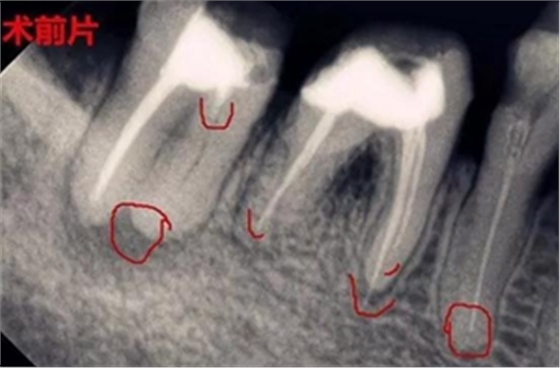

根管治療后長膿包怎么辦?

到這一步操作會更復雜,最好的方式就是先拍片檢查根尖部位,服用甲硝挫等藥片進行消炎,處理干凈瘺管周圍膿液,最后重新根管治療,要注意自己不能挑破,避免瘺管再次感染,另外單靠吃消炎藥只能治標不治本,還是會反復起膿包,我們建議

得到正規(guī)醫(yī)院檢查治療根尖周炎,確保根管治療的成功率。

所以根管治療清理干凈殘髓至關重要,還有牙膠尖一定要完整填充根管,不能出半點差錯,否則牙齦上的膿包會越變越大,及時排膿消炎減少瘺管感染,牙齦也可以慢慢恢復正常